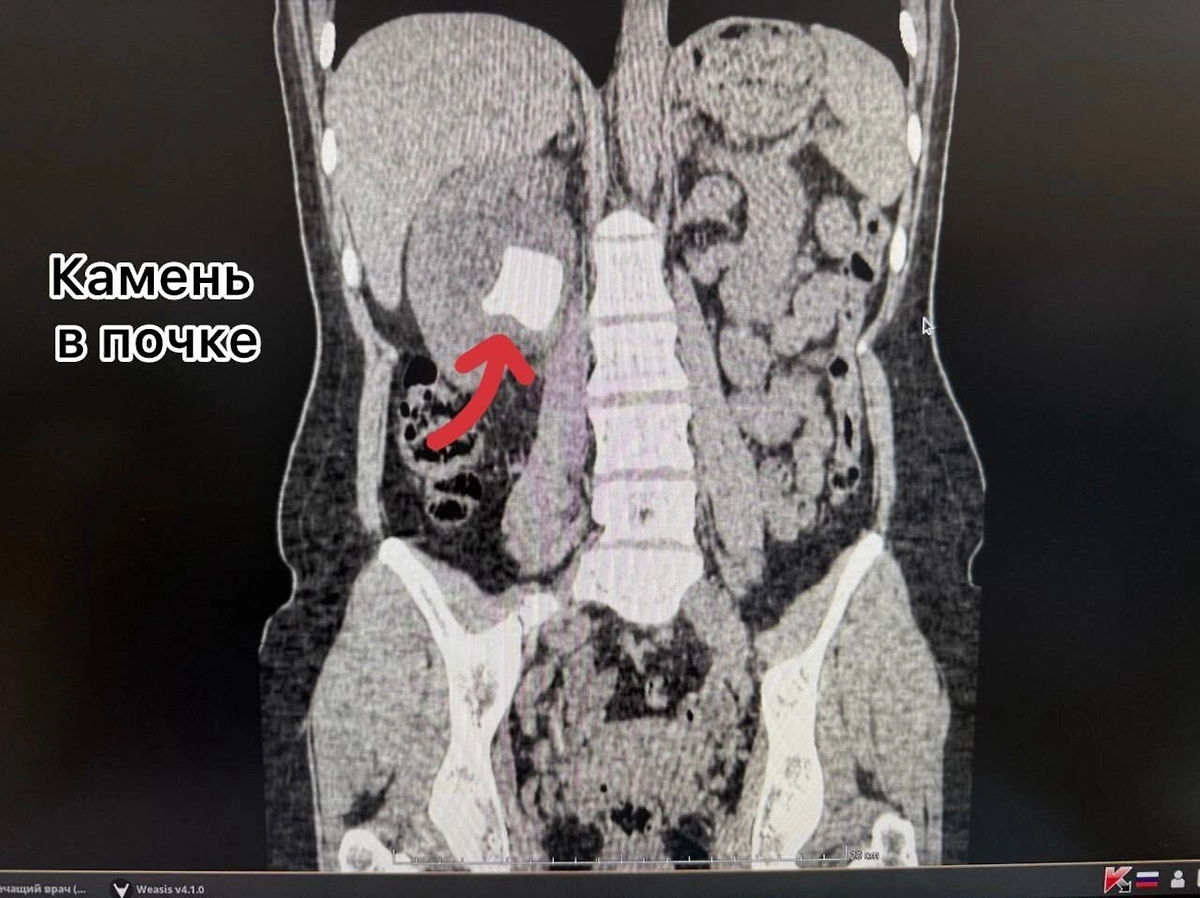

Как оказалось, два года назад женщине установили мочеточниковый стент, но вовремя его не удалили, из-за чего инородный предмет превратился в плотную структуры, а в почке и мочевом пузыре образовались камни. Врачи за раз провели многоэтапную операцию — удалили и стент, и образования в органах.

«Через один минимальный прокол в пояснице (метод перкутанной нефролитотрипсии) с помощью ультразвука был разрушен и удалён почечный камень. Одновременно, через естественные пути, современным лазером Urolase+ Premium был раздроблен и извлечен камень из мочевого пузыря и стент. Операция проводилась с применением эндоскопического оборудования и под рентген-контролем, что гарантировало высочайшую точность», — говорится в сообщении.

Рентген женщины с вросшим стентом во Владивостоке. Обложка © Telegram / Тысячекоечная больница г. Владивосток